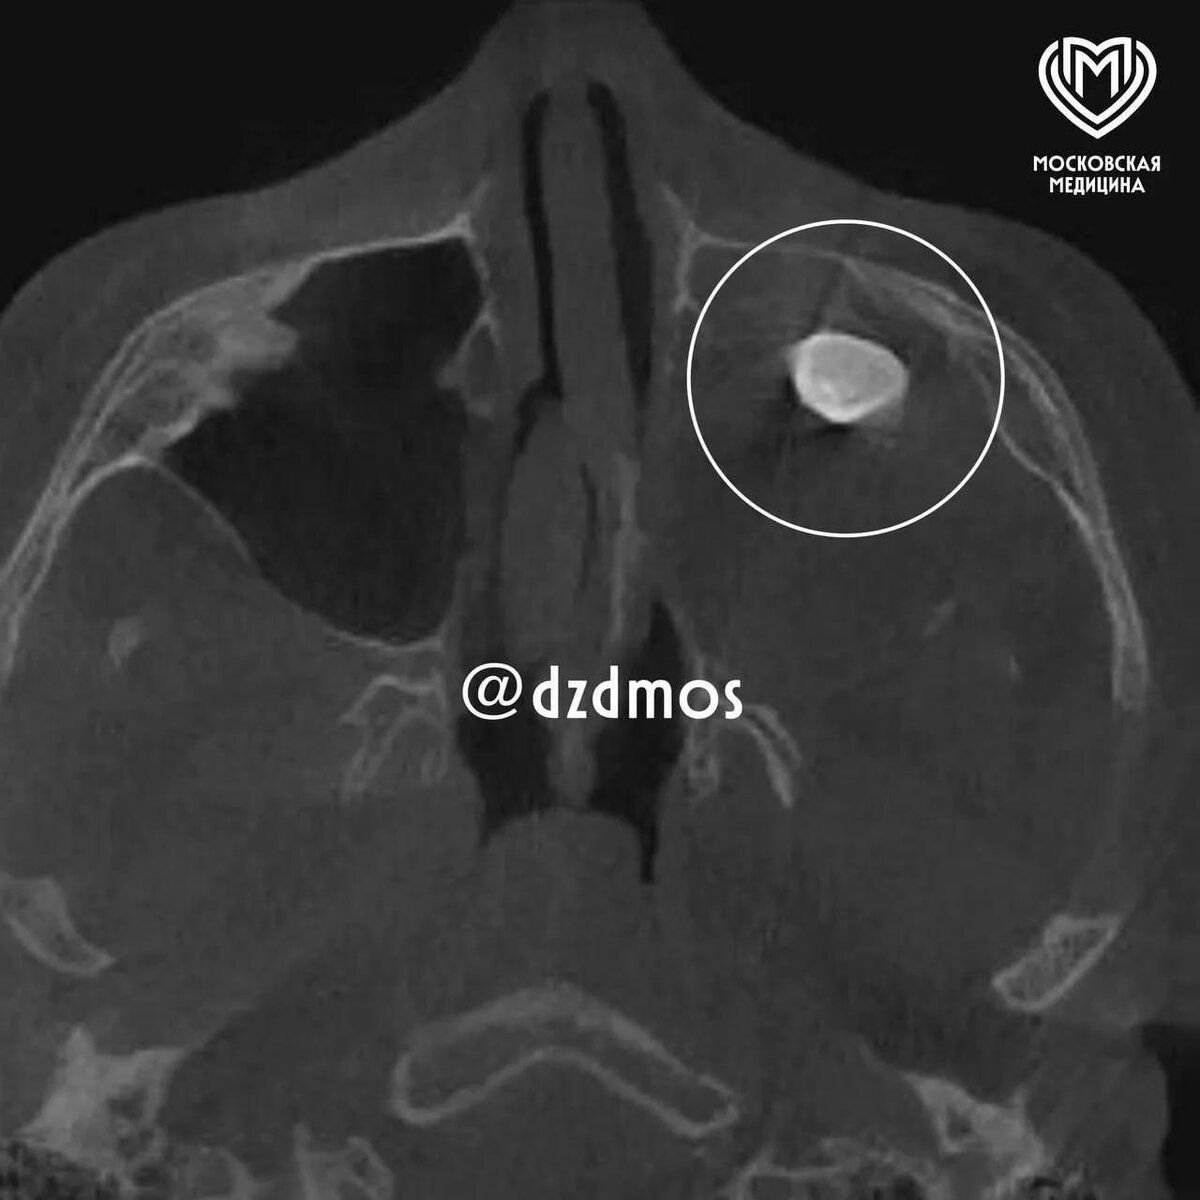

Московские врачи столкнулись с уникальным медицинским случаем: у подростка в носу обнаружен... зуб. Да, вы не ослышались — зуб! Это не сценарий фильма ужасов, а реальная история, которая демонстрирует, насколько сложен и иногда непредсказуем человеческий организм.

Зуб оказался частью тератомы — редкого образования, которое может содержать ткани, совершенно нетипичные для места его появления. Внутри тератомы могут находиться волосы, ногти, кости и даже зубы. Это происходит из-за сбоя в эмбриональном развитии, когда клетки начинают формировать структуры, которые им не положены.